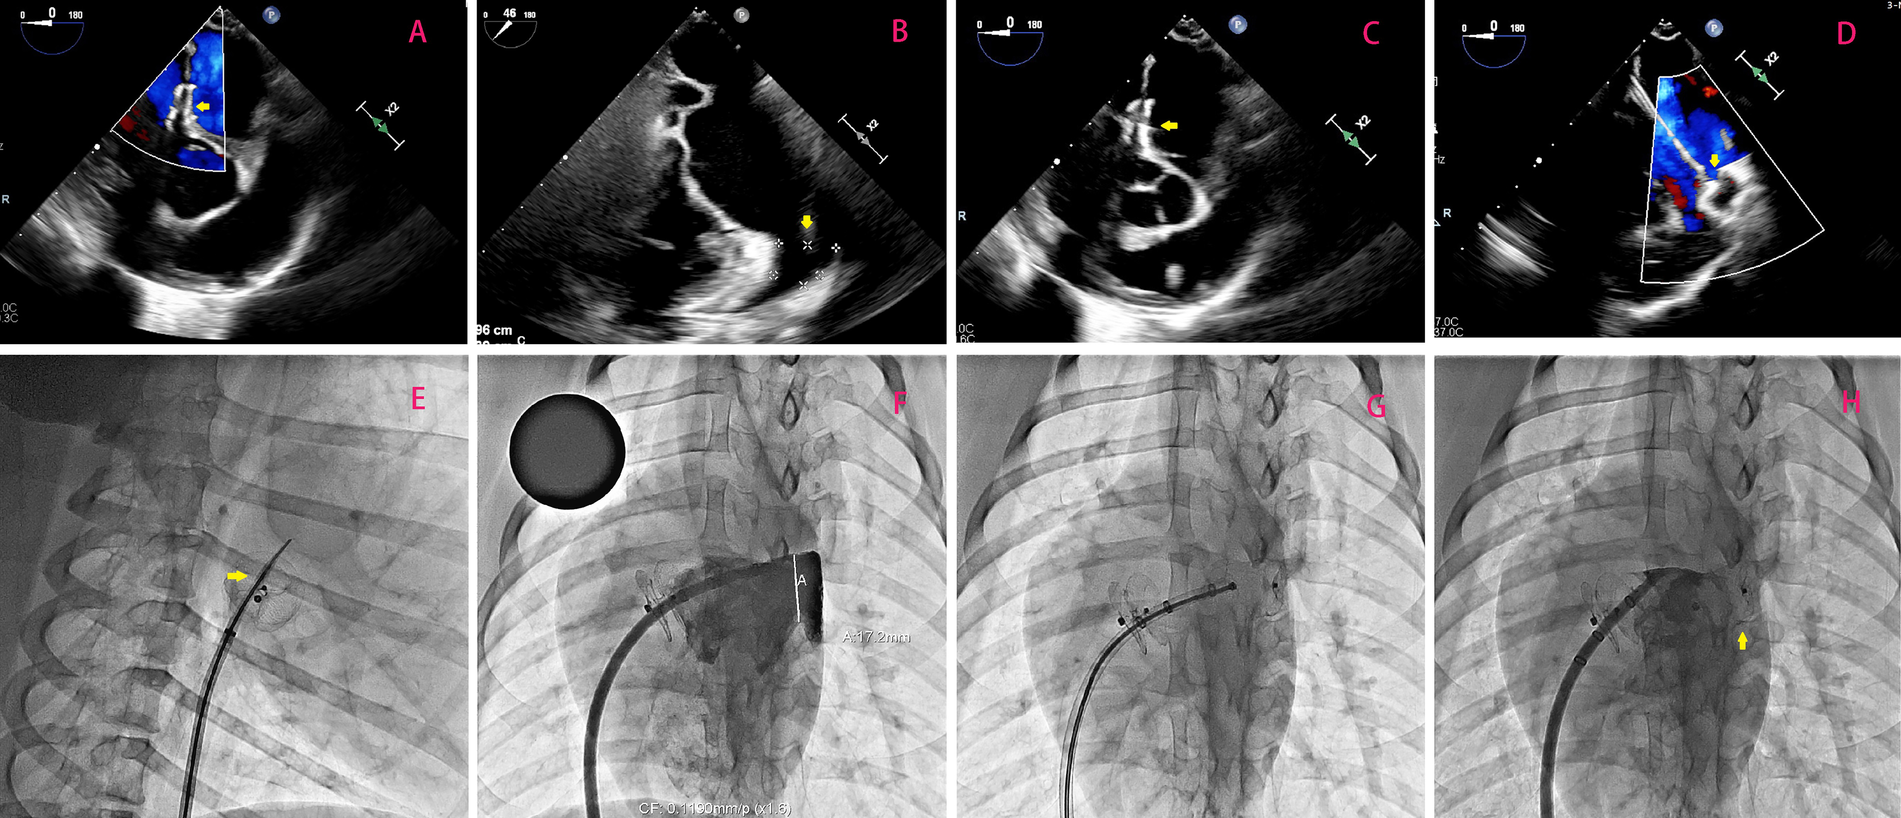

Figure 2

(A) Illustrates optimal positioning of the occluder without any observable shunting, as confirmed by a follow-up transesophageal echocardiogram 3 months after transcatheter PFO closure; the occluder is highlighted by the yellow arrow. In (B), emphasis is placed on measuring the dimensions (width and depth) of the left atrial appendage orifice, with its location indicated by the yellow arrow. (C) Demonstrates successful puncturing of the atrial septum through the PFO occluder under TEE guidance. Highlighted by the yellow arrow is the puncture needle. Lastly, in (D), TEE-guided LAAC is depicted with a focus on highlighting using a yellow arrow. (E–H) Shows the surgical procedure of percutaneous left atrial appendage occlusion using a new occluder under DSA fluoroscopy.

All six porcine subjects underwent successful creation of artificial PFO defects via balloon dilation, with no procedural complications. Immediate post-implantation evaluation using transesophageal echocardiography (TEE) and digital subtraction angiography (DSA) confirmed optimal device positioning in all cases (Figure 2A). No residual shunt was detected, and both discs exhibited complete apposition to the atrial septum. Device stability was further validated by the absence of dislodgement, thrombus formation, or arrhythmias during the initial 24-hour postoperative period.

Transseptal access and LAAC feasibility

At 3 months post-PFO closure, transseptal puncture through the occluder's designated puncture zone was attempted in all animals. Under fluoroscopic guidance, the tantalum-marked central area was successfully targeted in 6/6 cases (100% success rate), enabling precise needle penetration (Figure 2C). A stiff guidewire was advanced into the left upper pulmonary vein without resistance, followed by sequential balloon dilation (5 mm non-compliant balloon, 18 atm) to facilitate sheath insertion (12–14 Fr). Left atrial appendage closure (LAAC) was subsequently performed, with all occluders (bottle-shaped design) achieving complete deployment at the LAA orifice. Intraprocedural TEE and DSA confirmed absence of residual flow, pericardial effusion, or device-related complications (Figure 2D). The mean procedural time for transseptal puncture and LAAC was 32 ± 6 min, comparable to conventional septal access protocols.